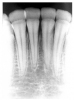

Taurodontism is a fairly common developmental defect in which the affected multi-rooted teeth display apically displaced furcation, producing a pattern of large pulp chambers and short roots. Clinically, the teeth appear normal, but on a radiographic image, they demonstrate a distinct rectangular outline, such as seen in tooth #19 in Figure 36

Pyramidal teeth are morphologically similar to taurodontism. They exhibit enlarged, elongated pulp chambers but only single roots, as illustrated in tooth #18 in Figure 36. In effect, the condition appears to represent extreme apical displacement of the furcation, resulting in a single broad root, which, in actuality, is the body of the tooth. The clinician will sometimes encounter both taurodontism and pyramidal teeth in the same patient.

Figure 36 - Pyramidal in #18; Taurodontism in #19

Figure 36